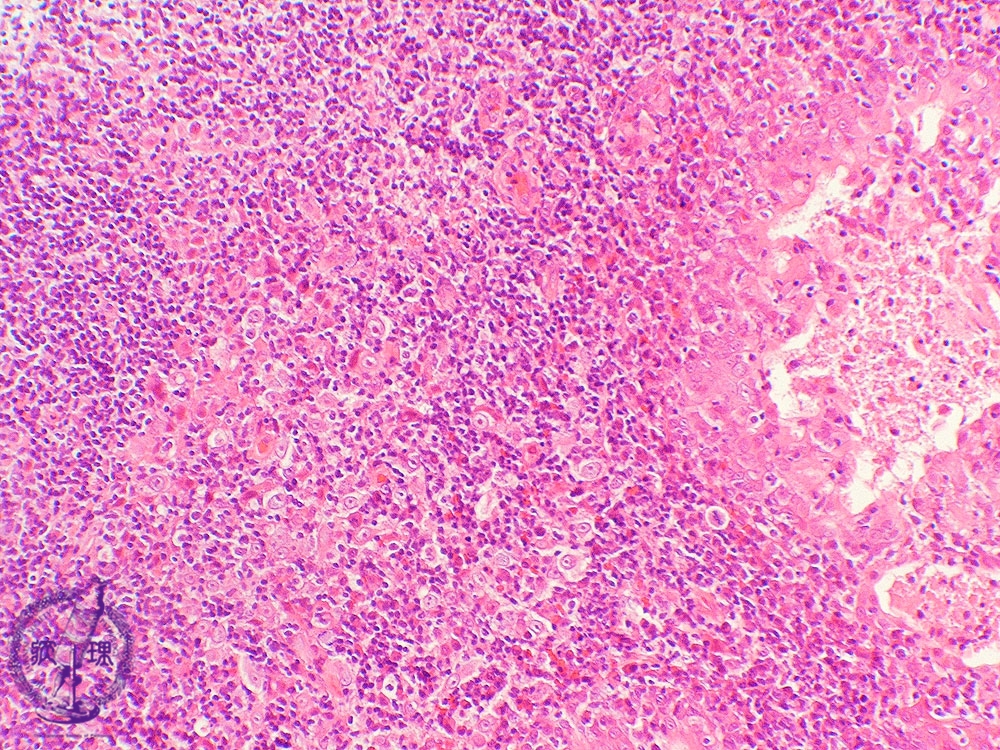

Microscopic view (intermediate power view): The most common subtype of nasopharyngeal carcinoma, undifferentiated carcinoma, is also known as elymphoepitheliomaf since there are abundant lymphocytes surrounding the carcinoma cells.